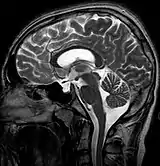

![]() | |

MRI of Empty Sella | |

Diagnostic method | MRI, CT scan[1] |

Empty sella syndrome is the condition when the pituitary gland shrinks or becomes flattened, filling the sella turcica with cerebrospinal fluid instead of the normal pituitary.[2] It can be discovered as part of the diagnostic workup of pituitary disorders, or as an incidental finding when imaging the brain.[1]